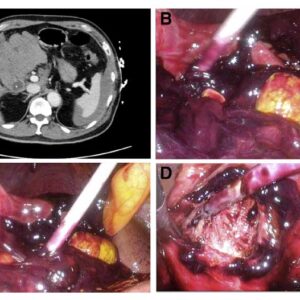

QUIZ: Uma causa rara de hemoperitônio

1 de maio de 20235 de abril de 2023

Notícias, Quiz